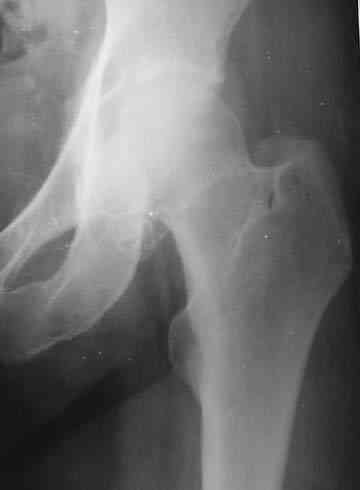

Боль постепенно усиливалась в течении последних 2 лет. Лечилась амбулаторно у невролога по месту жительства с диагнозом остеохондроз поясничного отдела позвоночника, корешковый синдром. В общих и биохимических анализах крови изменений не отмечалось, ревматоидный фактор (РФ), С-реактивный белок – в пределах нормы. Рентгенологическое исследование. В прямой и боковой проекции левого тазjбедренного сустава отмечается уплотнение крыши вертлужной впадины. В мягких тканях определяются округлой формы участки неравномерного обызвествления. Заключение. ДОА тазобедренного сустава. Хондроматоз слева в мягких тканях. Клиника. Видимых деформаций в области тазобедренного сустава нет. Ограничено отведение в левом тазобедренном суставе из-за болей до 20º. На основании клинических и лабораторных показателей был поставлен диагноз "Хондроматоз левого тазобедренного сустава". После стандартного предоперационного обследования выполнена диагностическая артроскопия тазобедренного сустава – обнаружены свободно лежащие внутрисуставные хондральные тела > 2 см в диаметре, хондромаляция хряща головки бедренной кости II степени. Выполнена боковая артротомия, внутрисуставные тела удалены, синовиальная оболочка частично резецирована. Послеоперационное течение – без осложнений. Швы сняты в срок, заживление первичным натяжением. Назначен курс лечебной физкультуры. Учитывая наличие рентгенологических признаков коксартроза, проведен курс внутрисуставной вискосуплиментарной терапии препаратами 1% гиалуроновой кислоты № 2. Осмотр через 1 месяц после оперативного лечения. Жалоб на боль при ходьбе нет, движения в полном объеме. Рекомендовано динамическое наблюдение раз в полгода и контрольная рентгенография через год